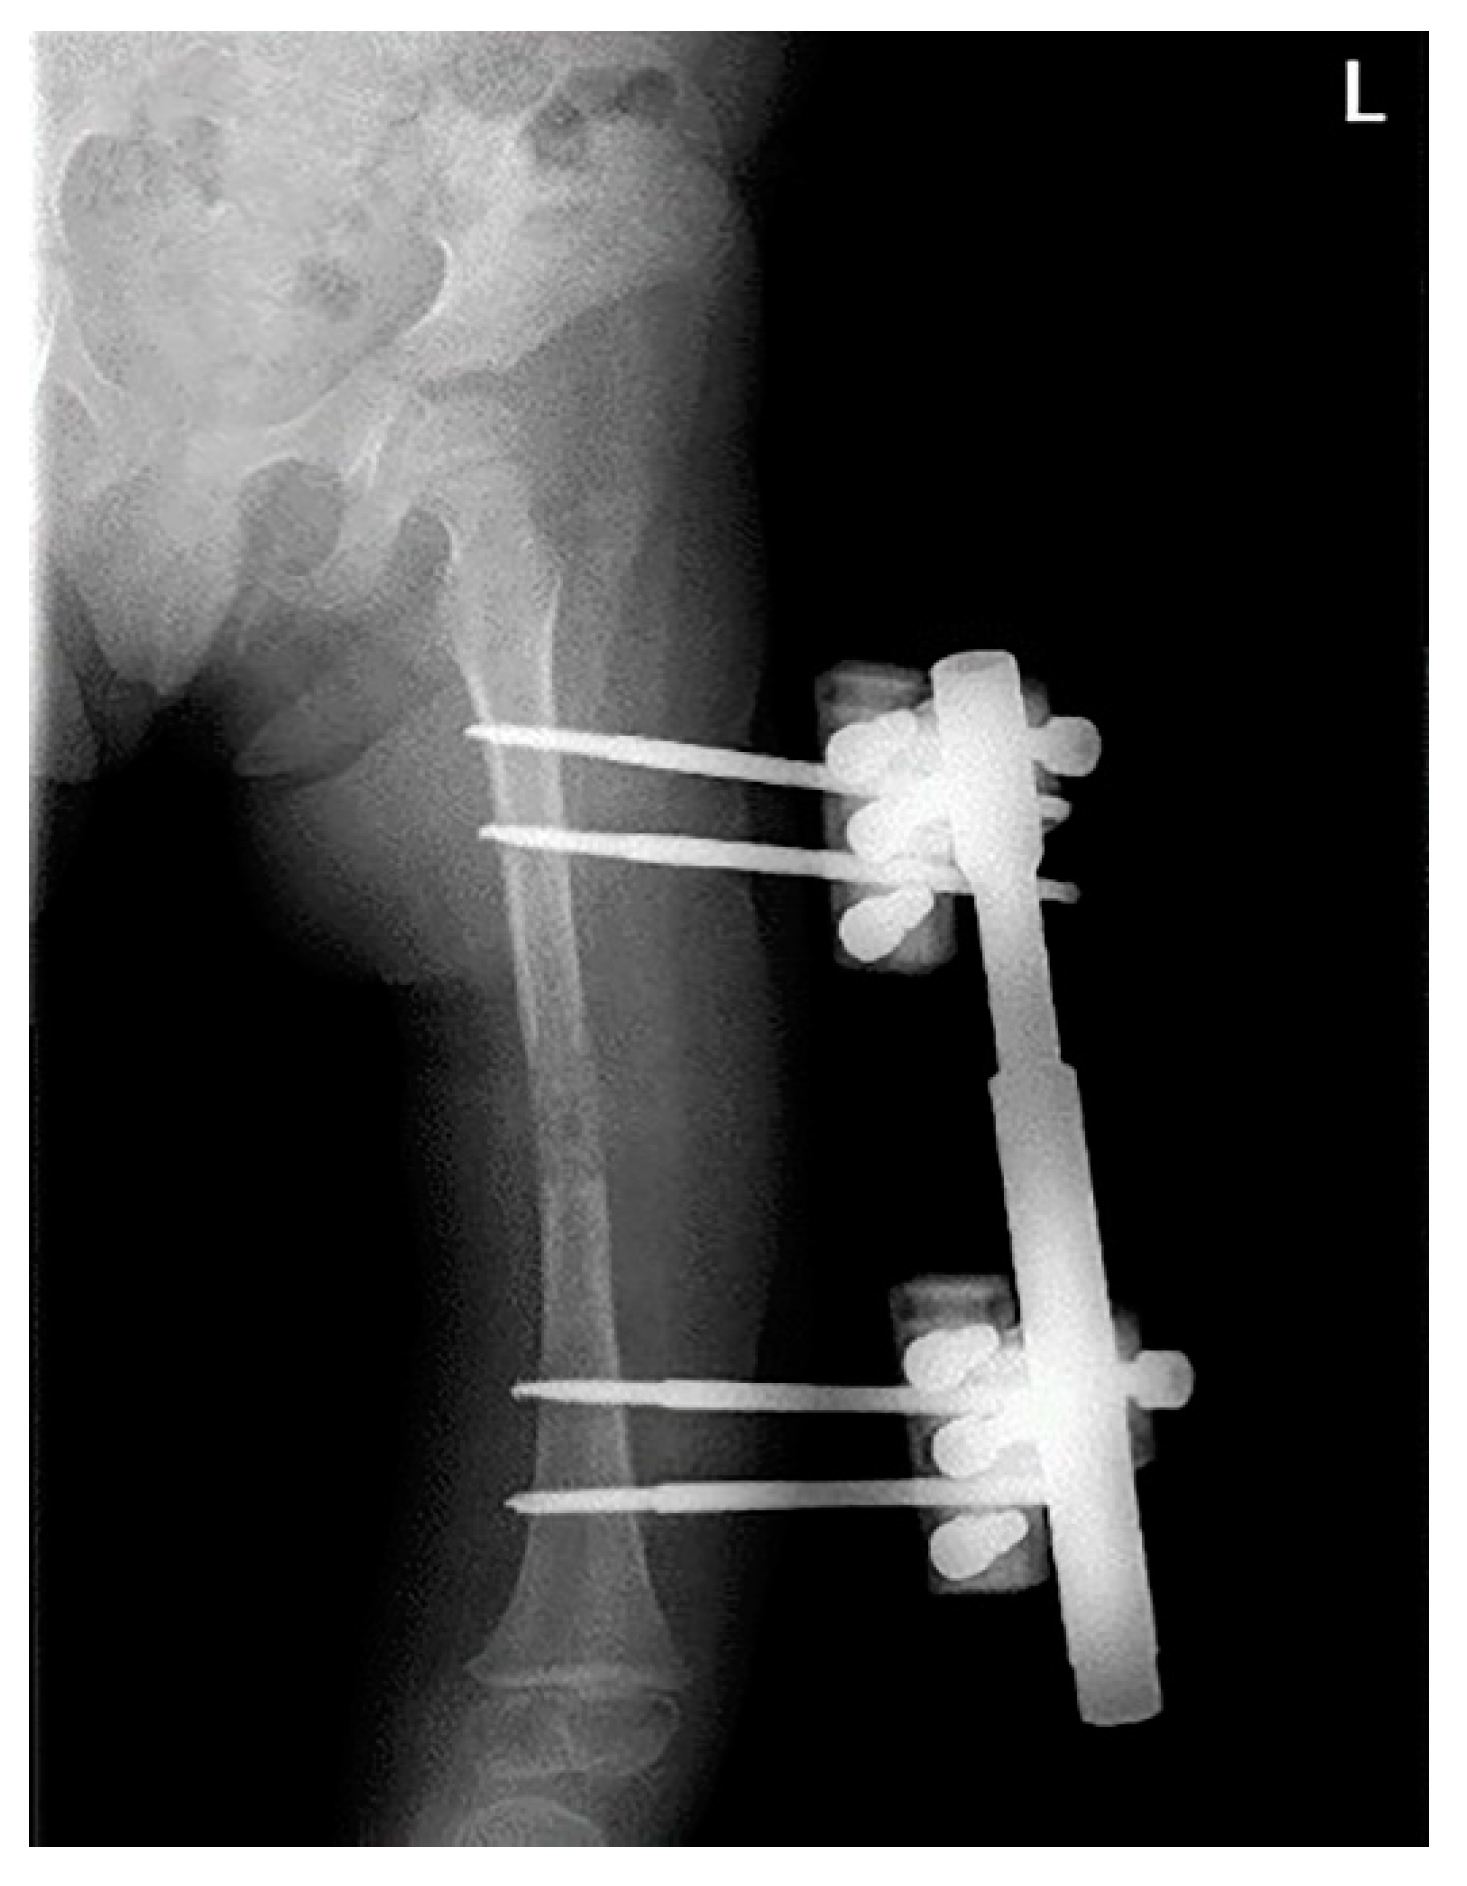

2. Case Description